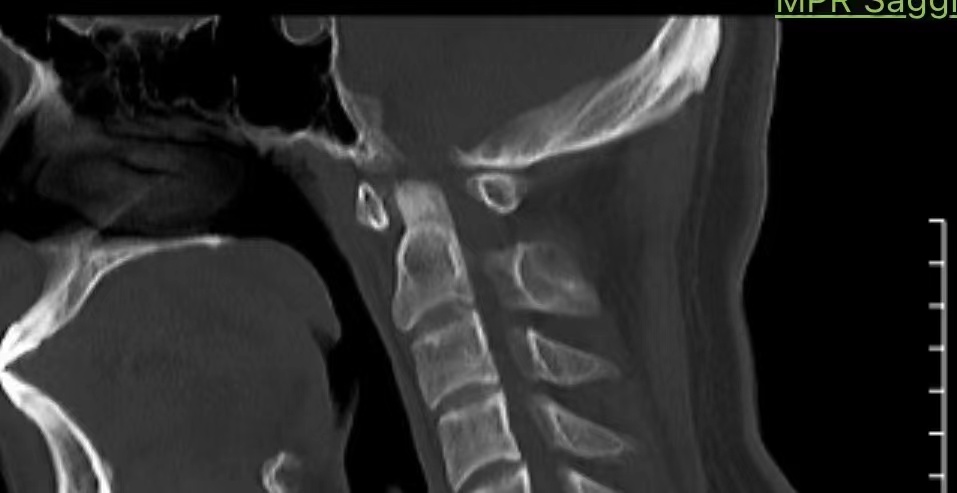

• 诊断:寰枢椎脱位

• 影像:

• 术后状况:术前患者同意不放融合器,术中切了后宫,术后复位还不错

• 术后影像: